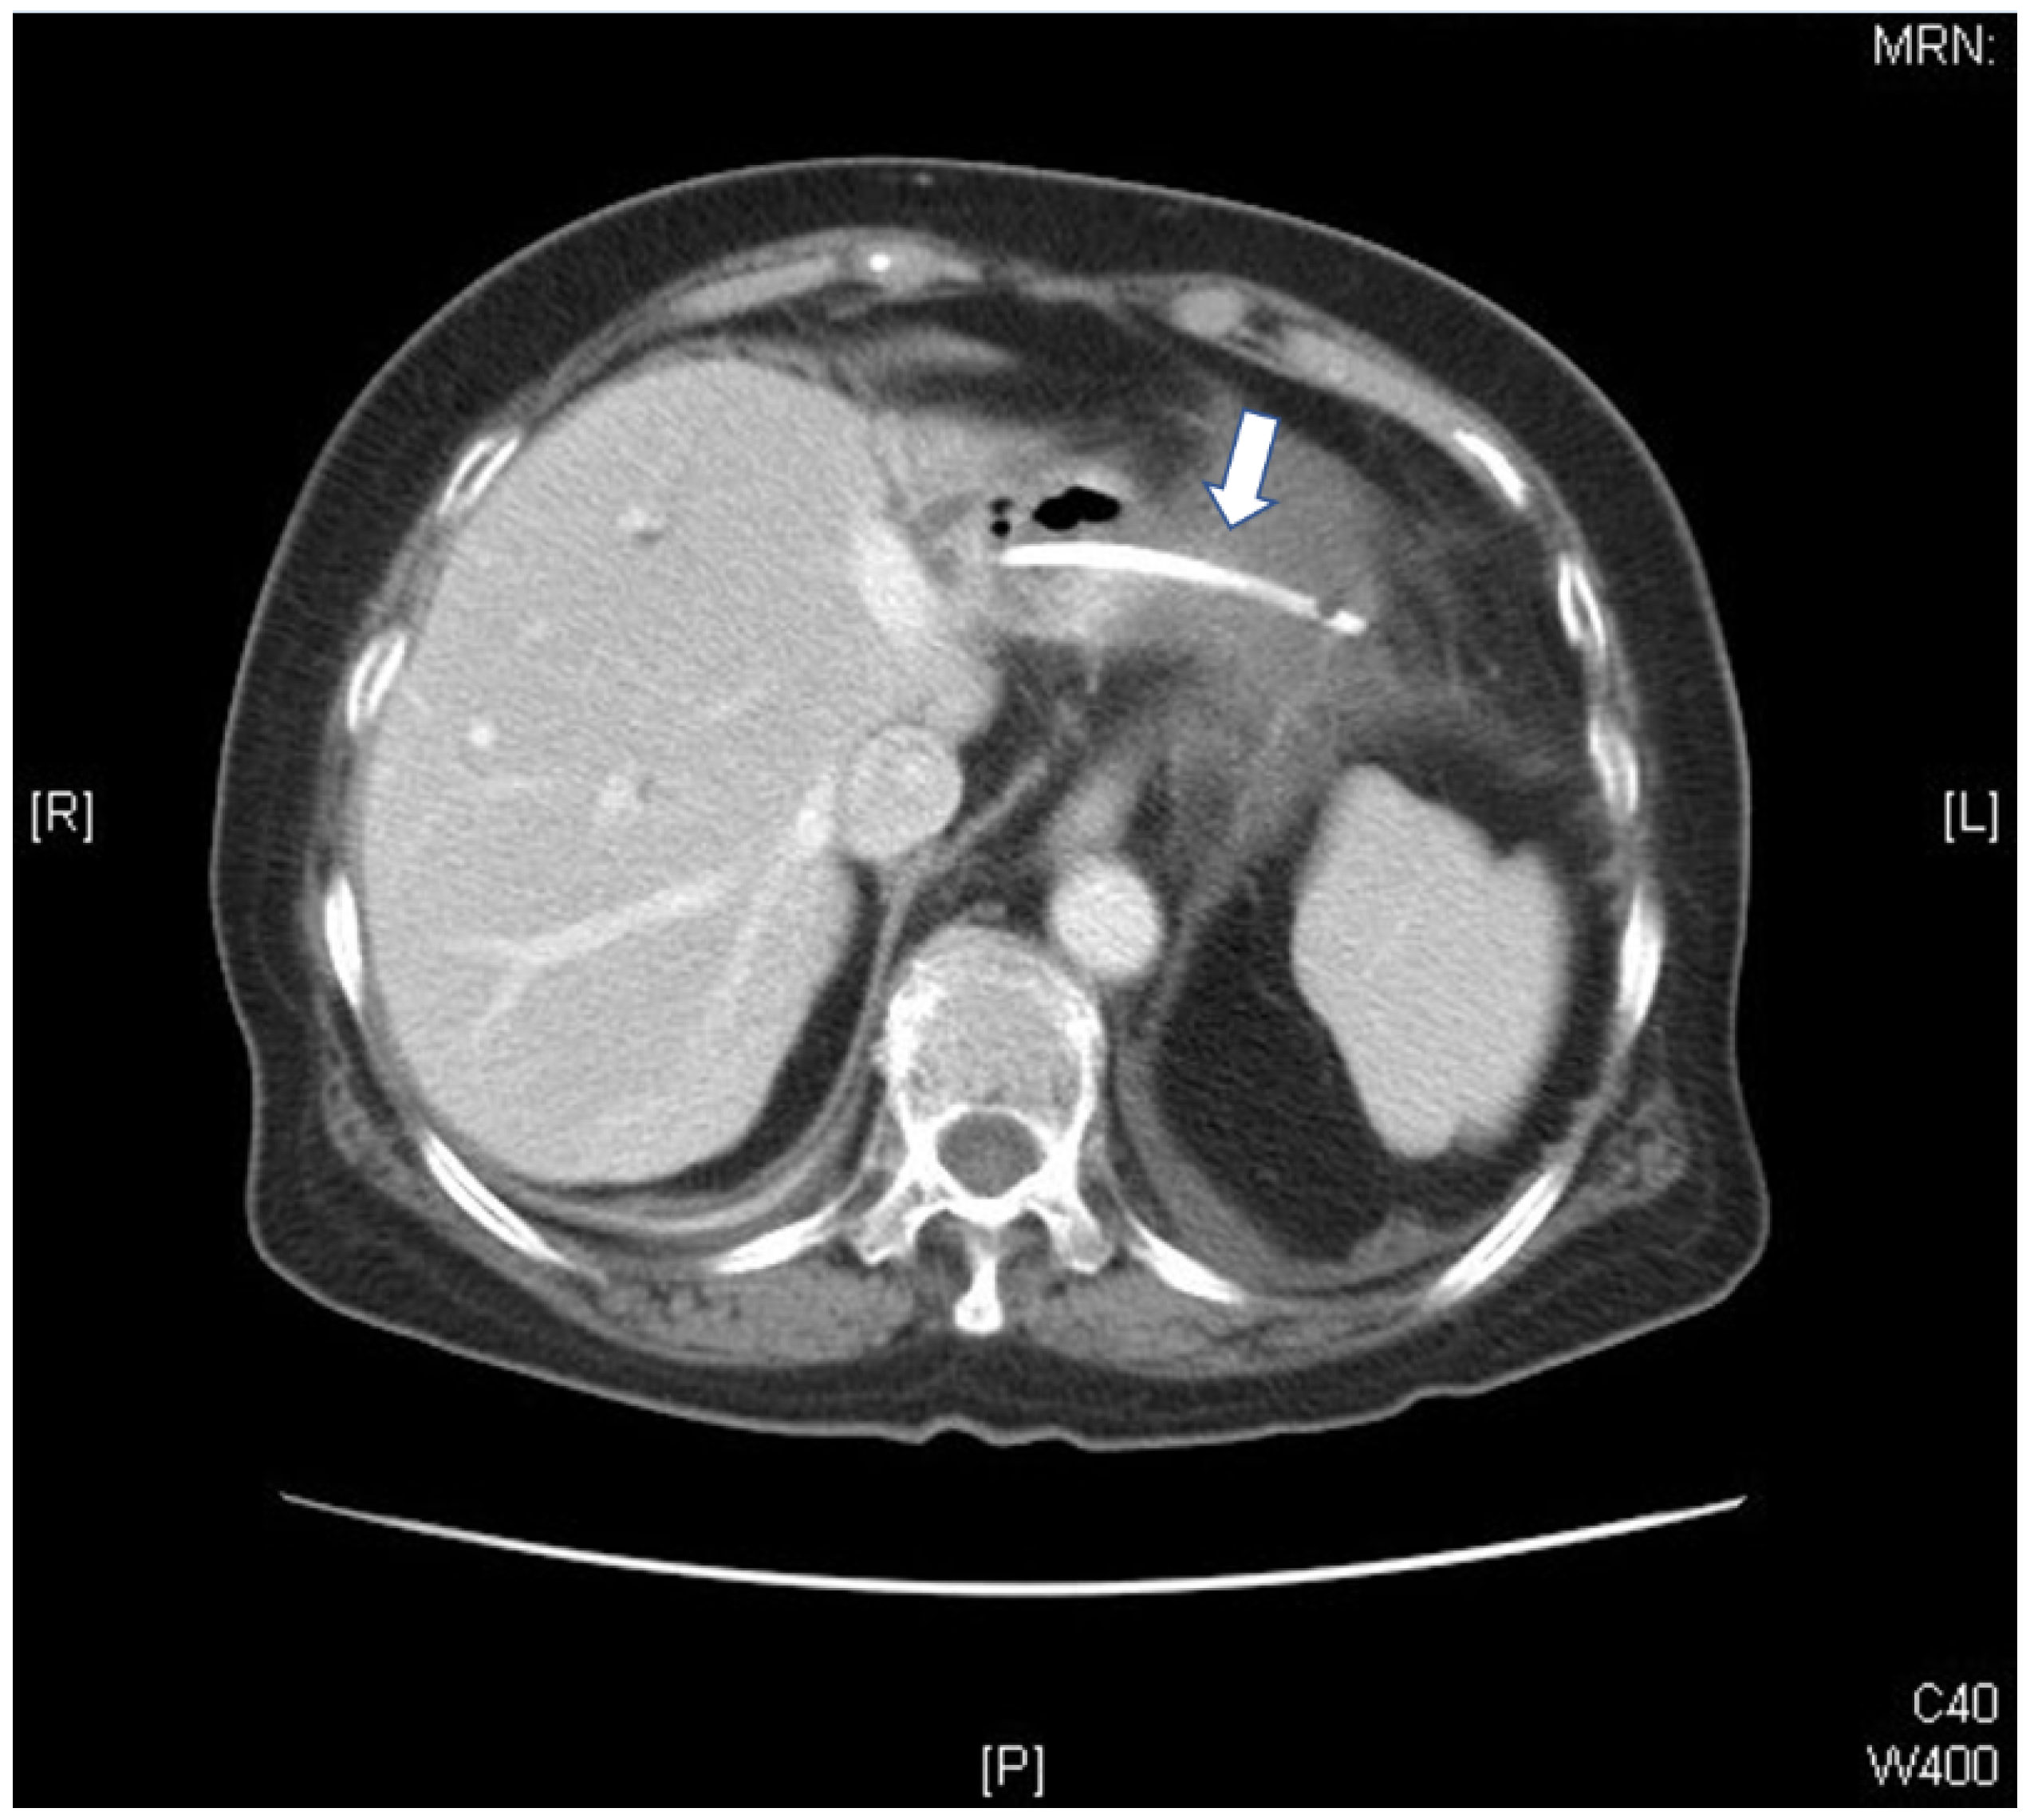

Bacterial Pericarditis Caused by Penetration of a Migrated Biliary Stent from the Lateral Segment of the Liver: A Case Report

2. Case Report